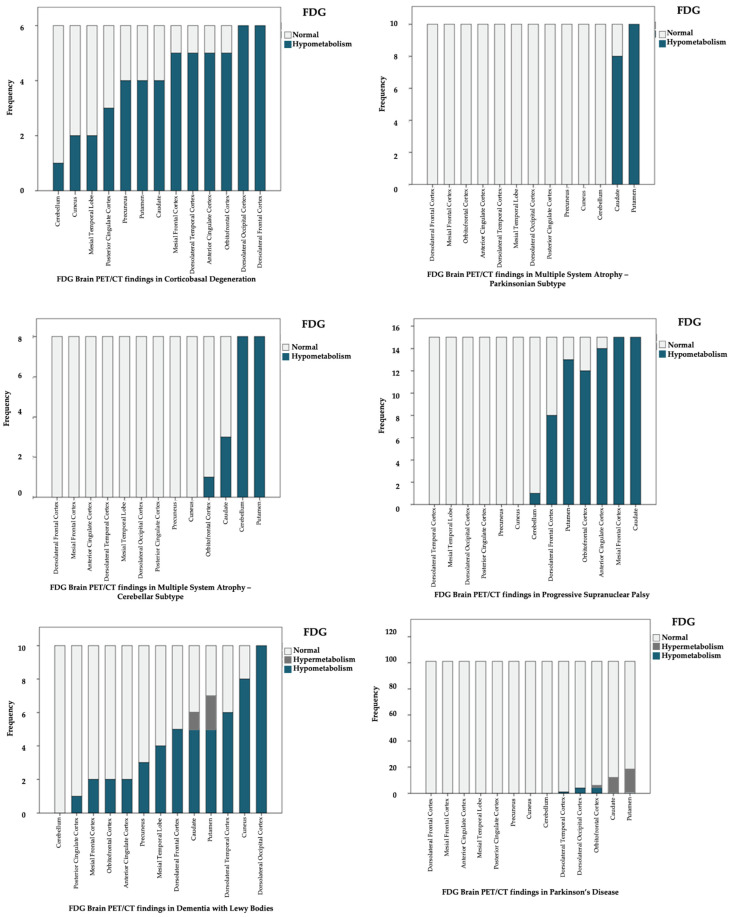

3.3. Brain [18F] FDG PET/CT Findings

Disturbances in glucose metabolism were observed in 47.33% of the patients. Normal metabolic findings were more frequent in patients diagnosed with PD, where overall normal cortical metabolism was observed alongside normal or hypermetabolism in the basal ganglia and hypometabolism in the parietal, occipital dorsolateral, and orbitofrontal cortex. In patients with atypical Parkinsonisms, metabolic alterations primarily affected the basal ganglia, with almost all cases presenting hypometabolism, except for DLB, where hypermetabolism in the striatum nuclei was also documented (Scheme 2).

Regarding FDG PET/CT findings, 52.67% of patients showed preserved metabolism, which can be explained by the fact that most patients had a clinical and dual PET/CT diagnosis of PD, in whom cerebral glucose metabolism is generally preserved. Metabolic patterns with FDG have been useful in the differential diagnosis of PD, as well as in atypical Parkinsonisms [ref. 29,ref. 30]. These findings correspond with those described by Garraux et al., who concluded that FDG PET/CT accurately distinguishes between PD and atypical Parkinsonisms, a relevant factor for prognosis and treatment [ref. 31]. Figure 1 summarizes the findings from dual FDOPA and FDG PET/CT in our population; until now, this had not been characterized in Mexico, and the results were similar to published data.